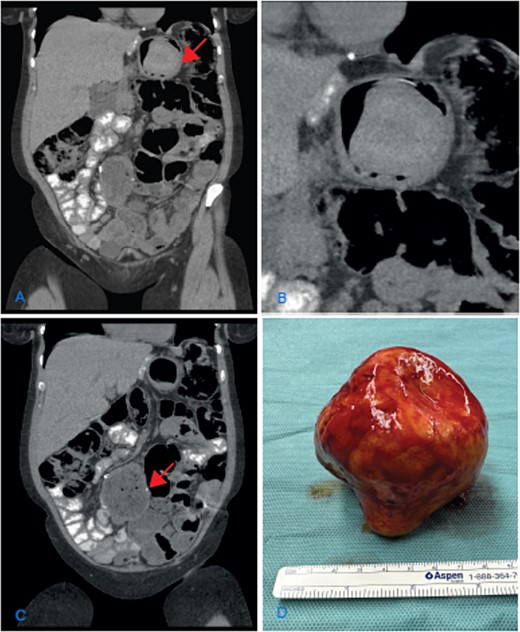

The clinical examination and lab results were normal. A gastroscopy did not reveal any pathological findings. The abdominal CT scan showed dilation of the jejuno-jejunostomy (JJ), biliopancreatic limb, and gastric remnant (Fig. 1A and C). Within the gastric remnant, hypodense mass of at least 5-cm diameter was detected (Fig. 1B). Considering the imaging findings, the patient was proposed for revisional surgery.

(A) Coronal CT scan image showing the dilatation of the gastric remnant with hypodensemass (arrow); (B) zoom of the gastric remnant with a 5-cm hypodense mass; (C) coronal CT scan image of the dilated JJ-anastomosis (arrow); (D) retrieved specimen a gallstone with approximately 10-cm diameter.

An elective laparotomy was performed. By palpation of the gastric remnant, a hard mass was detected. The specimen was retrieved through a gastrotomy. A hard yellow-brown stone ~10 cm in diameter was found intraluminally. After retrieving the intraluminal mass, the dilated side-to-side JJ-anastomosis was resected and reconstructed in an end-to-side fashion.